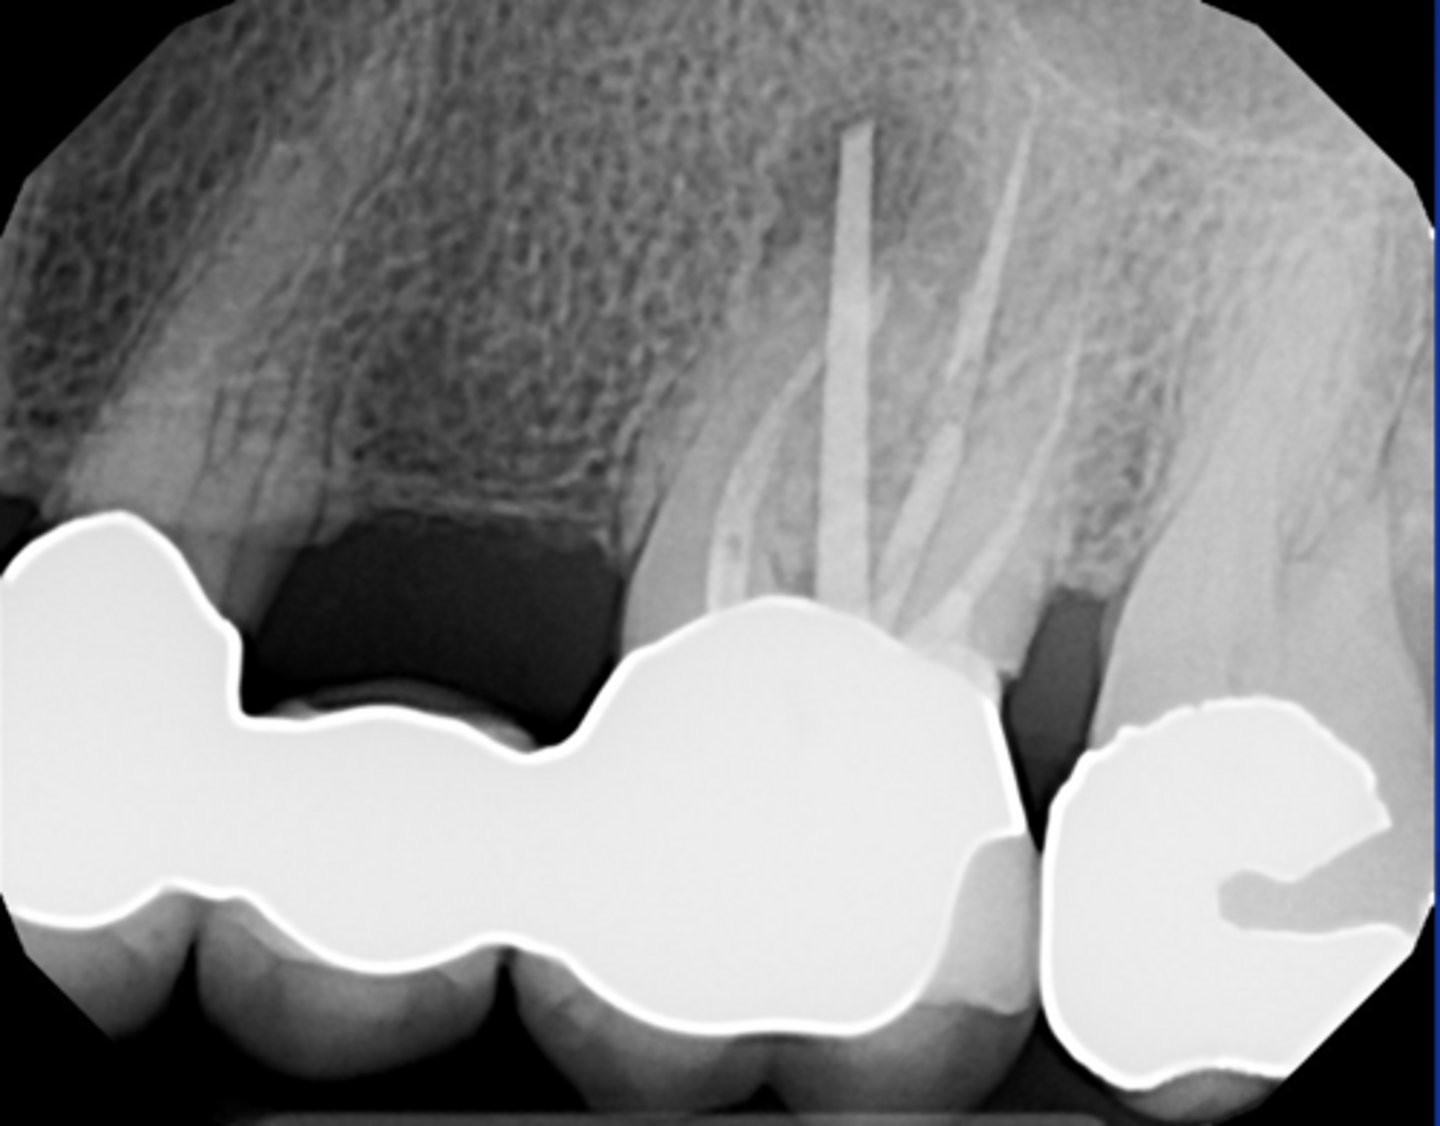

Check if missed MB2

RCT 10 years ago thru bridge

Sinus tract 3 years ago...apicoectomy done

Sinus tract returned.

What do we do?